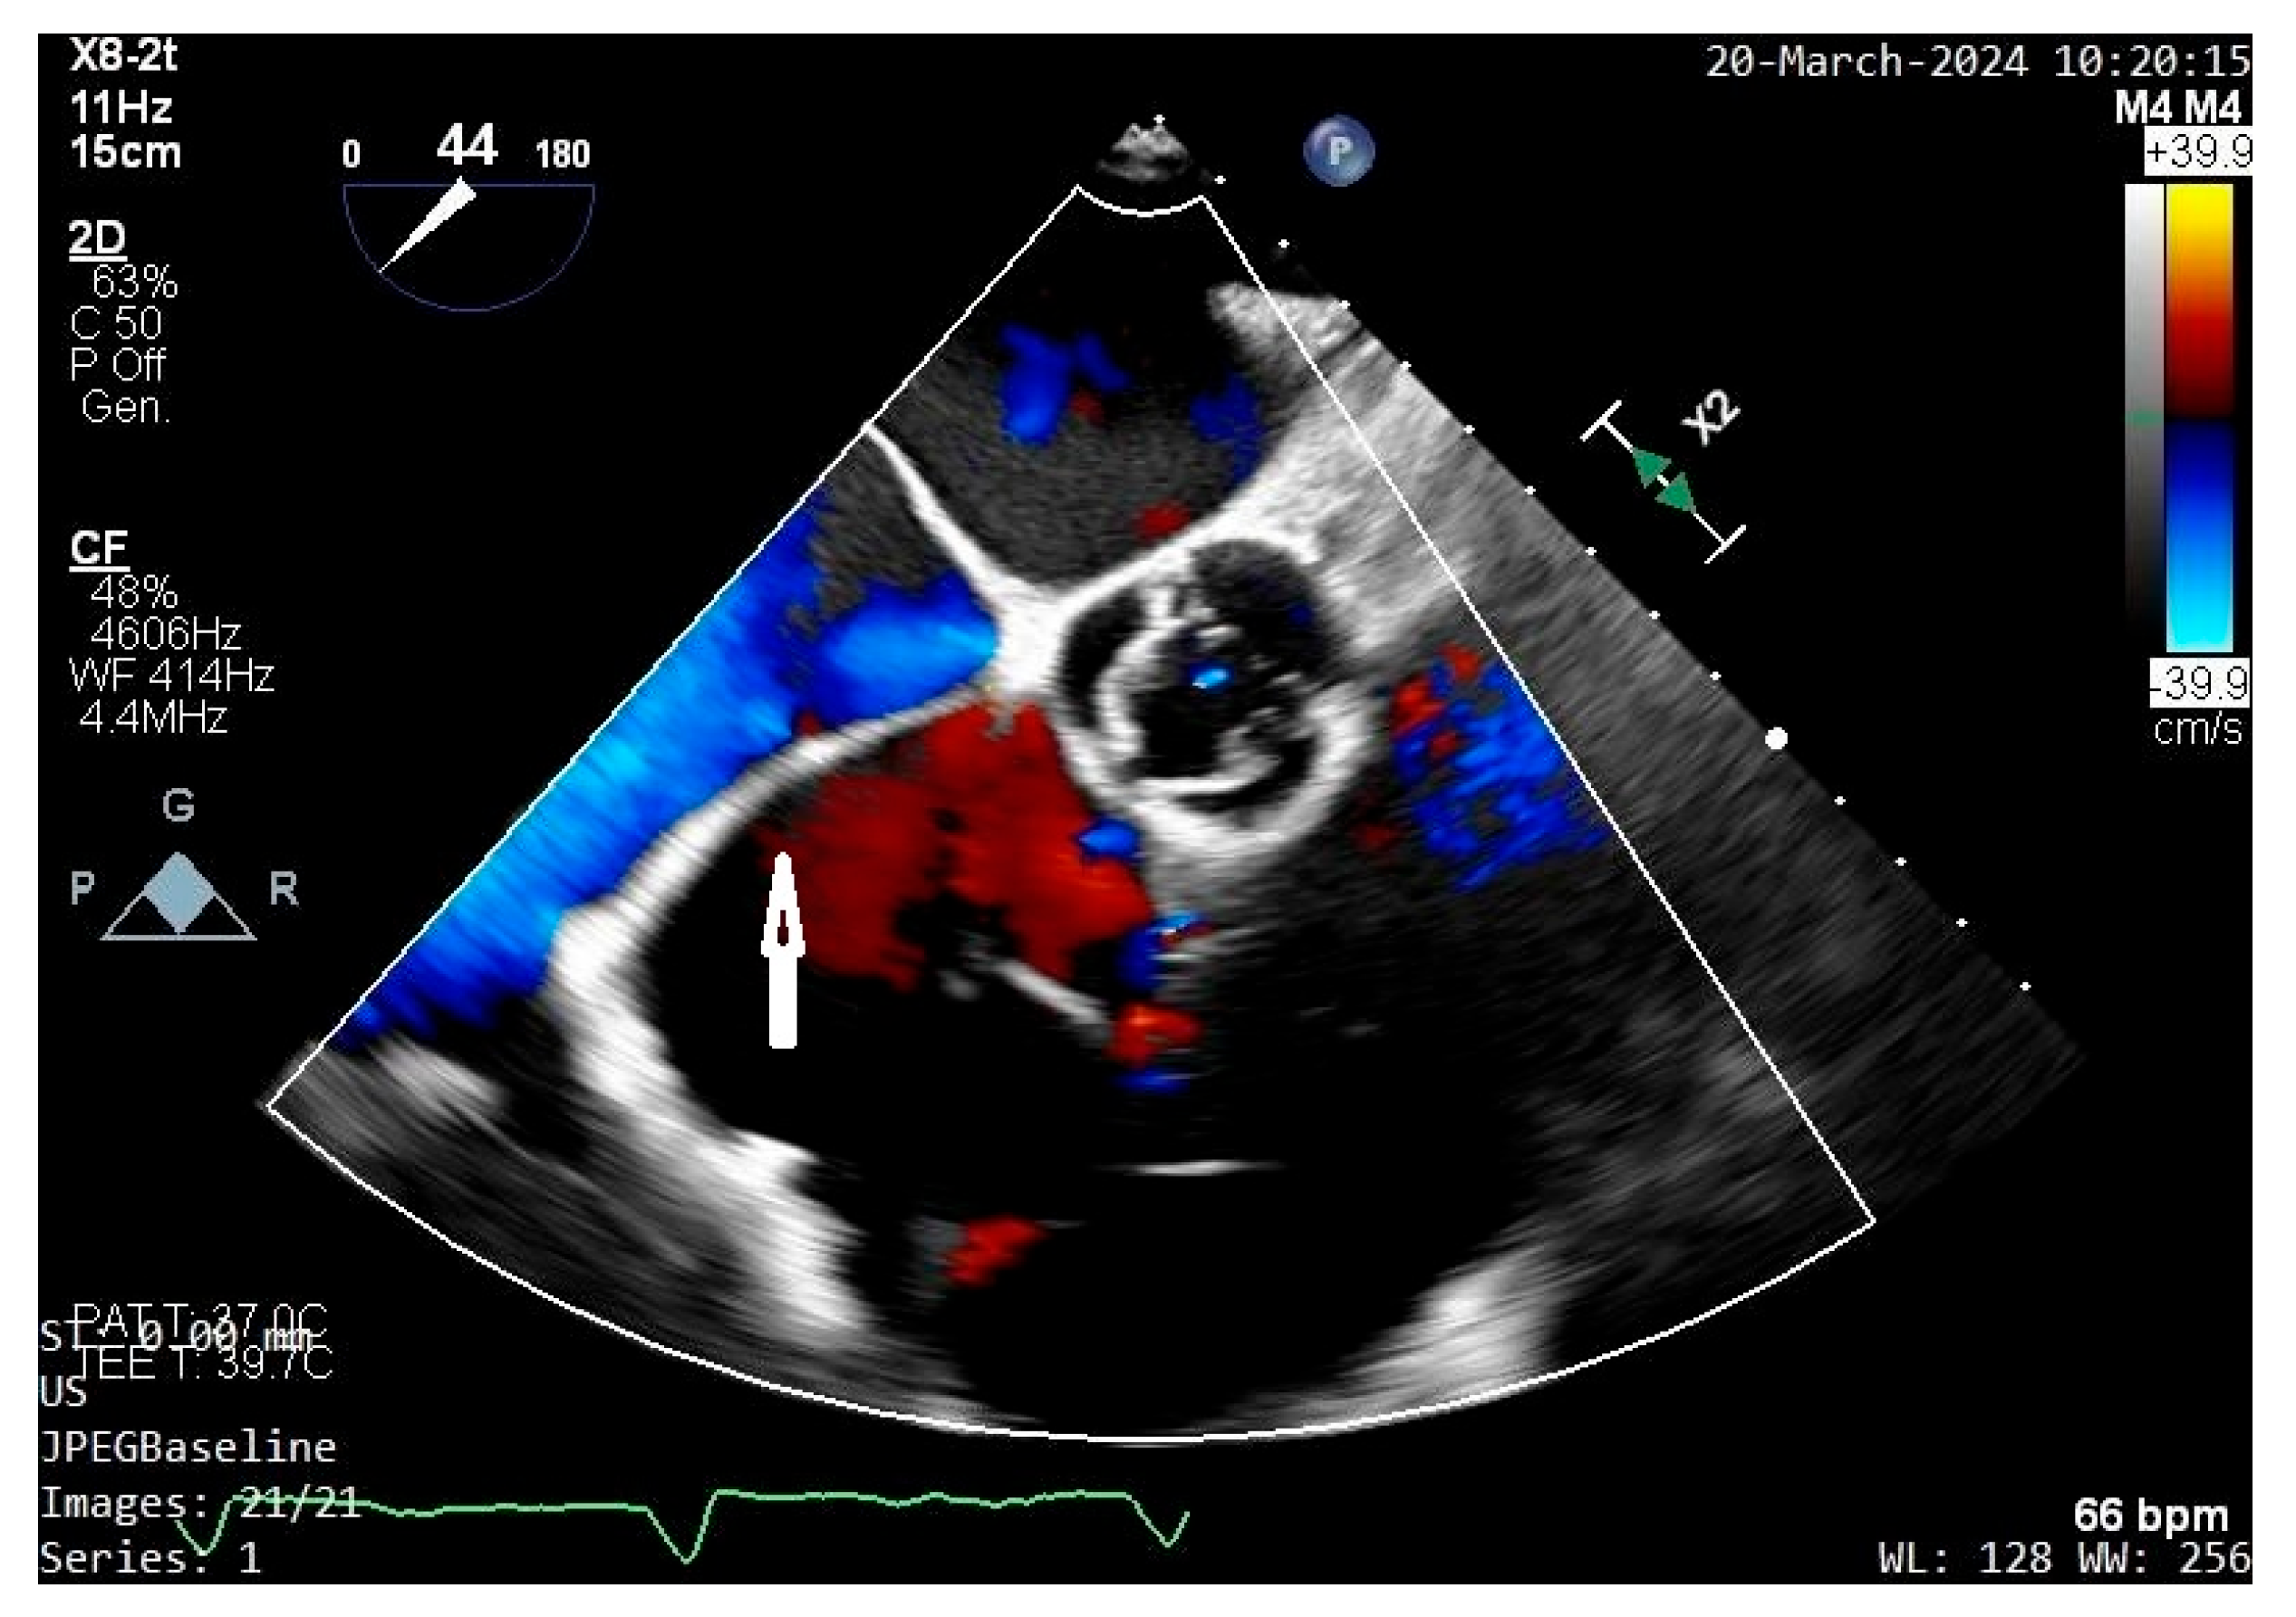

- Franco, E.; Rovera, C.; Moretti, C.; Bassareo, P.P. Arrhythmogenic Right Ventricular Cardiomyopathy and Cor Triatriatum Dexter: An Unreported Association. Clin. Case Rep. 2025, 13, e71159. [Google Scholar] [CrossRef]